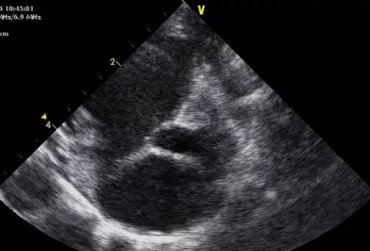

Dysplazja zastawki trójdzielnej i zespół Wolffa–Parkinsona–White’a u kota – opis przypadku

Zwężenie zastawki trójdzielnej jest jedną z form dysplazji pojawiającą się w różnym stopniu nasilenia (najczęściej łącznie z niedomykalnością zastawki) zarówno u psów, jak i u kotów. Cechami charakterystycznymi definiującymi zwężenie zastawki trójdzielnej są: obecność rozkurczowego wybrzuszenia (doming) płatków zastawki, zmniejszona ruchomość płatków, zmniejszona średnica ujścia zastawki. Mimo że zmiany morfologiczne aparatu trójdzielnego są typowe w przebiegu TVD i są znakiem rozpoznawczym tej choroby, nie są one zawsze bardzo silnie wyrażone i nie zawsze można mieć bezsprzeczną pewność diagnostyczną, bazując na badaniu echokardiograficznym [10]. Przypadki takie zdarzają się przede wszystkim u pacjentów, u których nie postawiono diagnozy we wczesnym etapie życia, a którzy pojawiają się na badaniu dopiero w starszym wieku z zaawansowanymi zmianami i niejednokrotnie z klinicznymi objawami prawostronnej niewydolności mięśnia sercowego i towarzyszącymi zaburzeniami w rytmie. W takich przypadkach obraz choroby może przypominać arytmogenną kardiomiopatię prawokomorową (arrhythmogenic right ventricular cardiomyopathy – ARVC) [1, 8]. Preekscytacja jest często obserwowana u ludzi z anomalią Ebsteina. U zwierzat, podobnie jak u ludzi, obecność dodatkowej drogi przewodzenia może nigdy nie prowadzić do rozwoju tachykardii nadkomorowej lub arytmia ta pojawiać się może dopiero w późniejszym okresie życia. Opisany przypadek jest przykładem pacjenta z dysplazją zastawki trójdzielnej i prawostronną niewydolnością serca będącą najprawdopodobniej konsekwencją tachykardii nadkomorowej.